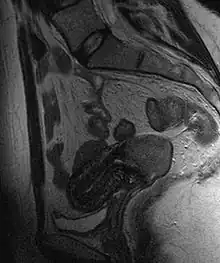

Often before the biopsy, the doctor asks for medical imaging to rule out other causes of a woman's symptoms. Imaging modalities such as ultrasound, CT scan, and MRI have been used to look for alternating disease, spread of the tumor, and effect on adjacent structures. Typically, they appear as heterogeneous masses on the cervix.[64]